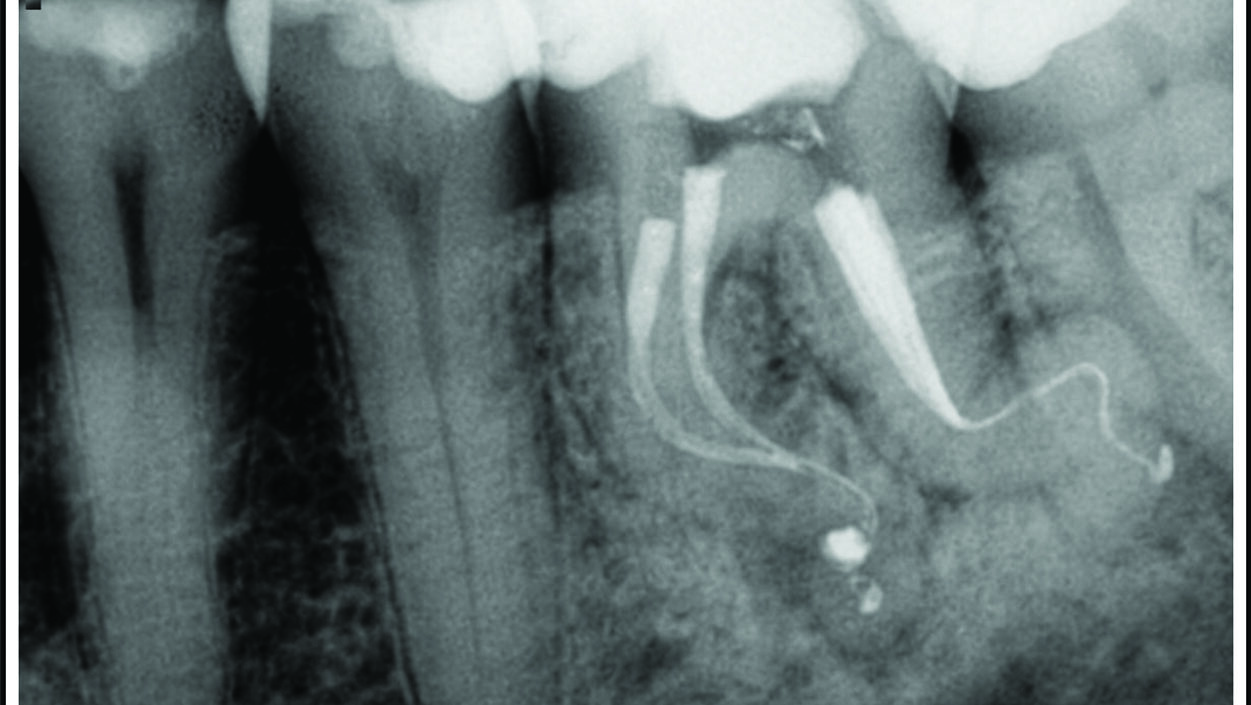

The most common odontogenic infection is that of the periapical tissues most frequently caused by dental caries, a deep restoration, or failed root canal treatment.1 Apical periodontitis (AP) has been found to have a prevalence of 50% in patients under the age of 50, and the prevalence and risk of AP has been found to be … Read more